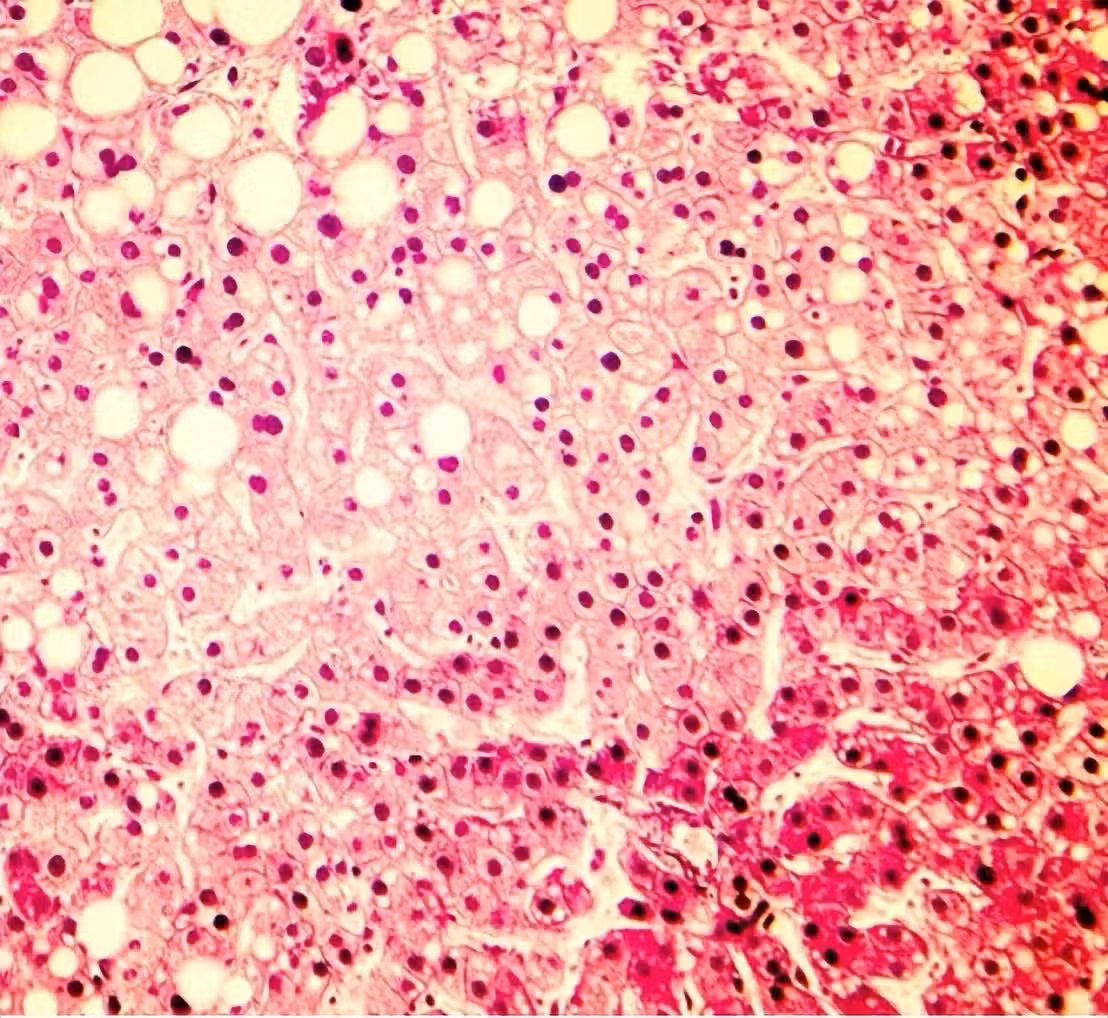

45歲中年女子確診脂肪肝,天天都吃番茄,3月後複診,醫生:怎麼吃的?

脂肪肝沒了「早上改吃2物」 她三個月瘦5公斤 醫師也點頭